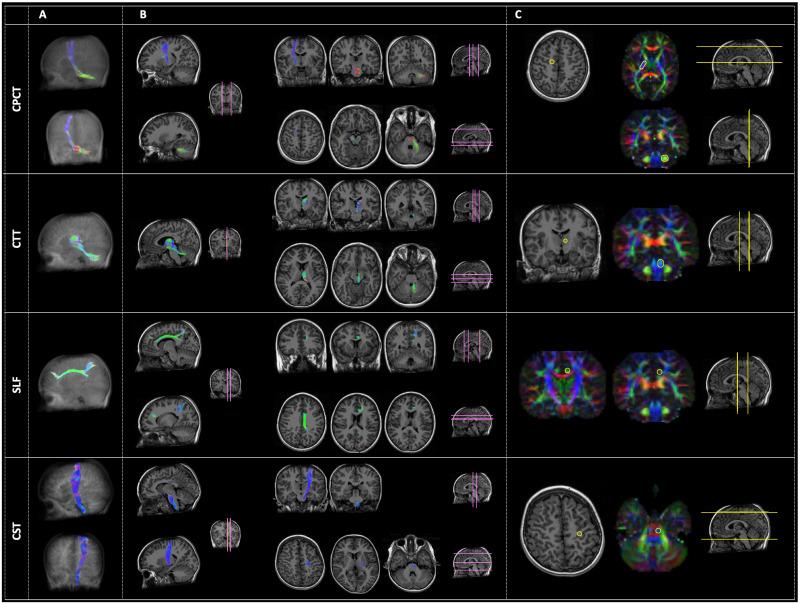

This pilot study included 15 boys (5 DMD subjects, 5 BMD subjects, and 5 age-matched typically developing, TD). They were assessed using a neuropsychological assessment protocol including cognitive and executive functioning assessment and performed a 1.5T MRI brain exam including advance Diffusion Weighted Imaging (DWI) method for tractography. Structural connectivity measurements were extracted along three specific tracts: Cortico-Ponto-Cerebellar Tract (CPCT), Cerebellar-Thalamic Tract (CTT), and Superior Longitudinal Fasciculus (SLF). Cortical-Spinal Tract (CST) was selected for reference, as control tract.

Regarding intellectual functioning, a major impairment in executive functions compared to the general intellectual functioning was observed both for DMD (mean score = 86.20; SD = 11.54) and for BMD children (mean score = 88; SD = 3.67). Mean FA resulted tendentially always lower in DMD compared to both BMD and TD groups for all the examined tracts. The differences in FA were statistically significant for the right CTT (DMD vs BMD, p = 0.002, and DMD vs TD, p = 0.0015) and the right CPCT (DMD vs TD, p = 0.008). Concerning DMD, significant correlations emerged between FA-R-CTT and intellectual quotients (FIQ, p = 0.044; ρs = 0.821), and executive functions (Denomination Total, p = 0.044, ρs = 0.821; Inhibition Total, p = 0.019, ρs = 0.900). BMD showed a significant correlation between FA-R-CPCT and working memory index (p = 0.007; ρs = 0.949).